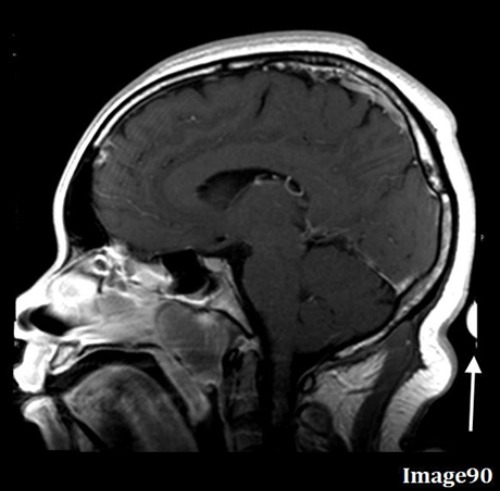

What is the most direct way to correct for the wrap-around artifact seen in Image 90?

A. Increase parallel imaging factor

B. Reduce FOV

C. Increase voxel size

D. Enable flow compensation

E. Increase FOV

The white arrow in Image 90 points to anatomy from the top of the head being wrapped to the bottom of the image. What is this artifact?

A. Motion/ghosting in the phase direction

B. Gibbs truncation

C. RF zipper

D. Wraparound (aliasing)

E. Magnetic susceptibility

To correct for the wrap-around (aliasing) artifact seen in Image 89, the technologist should:

A. Utilize oversampling

B. Utilize undersampling

C. Enable anti-aliasing option

E. A and/or C

F. B and/or C